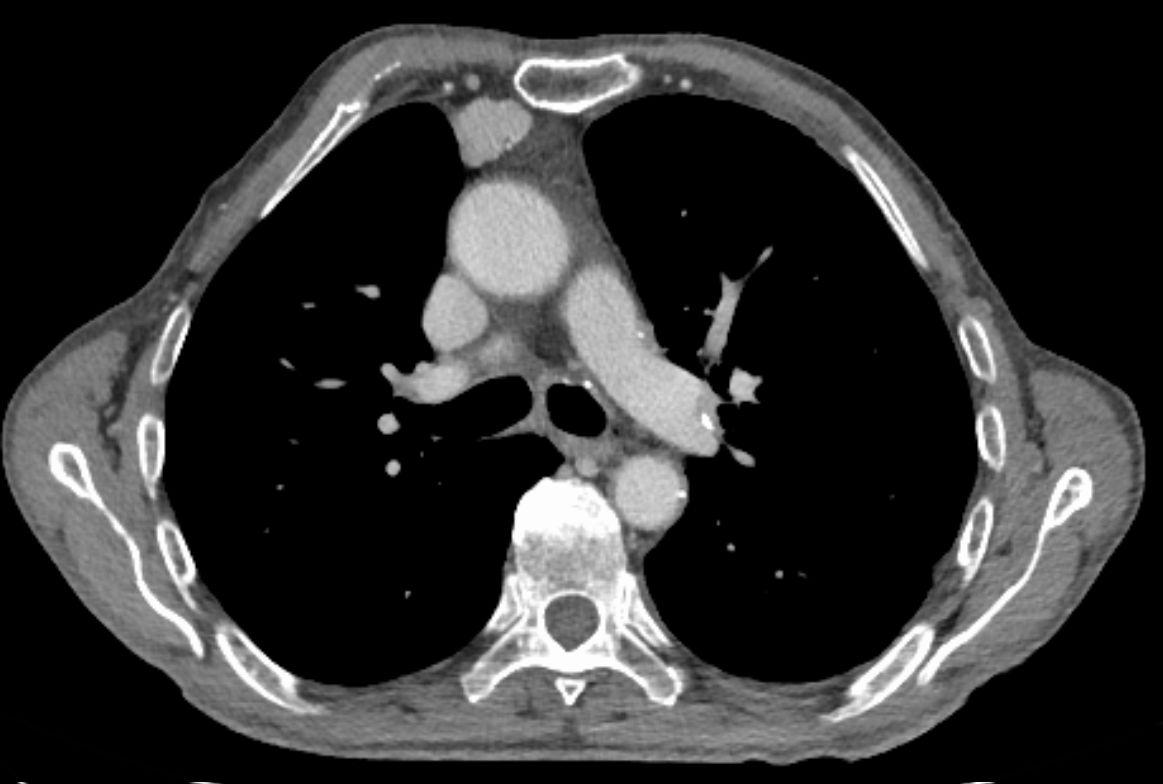

All three patients were found to have thymoma, which is a tumour in the thymic gland. They found that PIT-1 is expressed in these thymoma cells. CTLs then targeted PIT-1 and this caused the autoimmune response. When the researchers removed the thymus from patients with the autoimmune disease, the levels of anti-PIT-1 antibody and the effects of the CTLs specific to PIT-1 were greatly reduced. However, at 2 years post-thymus removal, there was no detectable improvement in pituitary function.